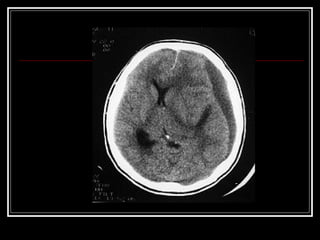

Hematoma subdural agudo

 localizado entre as membranas que revestem o cérebro

 é encontrado em pacientes que sofrem traumatismo

decorrente de aceleração e desaceleração em altas

velocidades.

 Pode ser simples e tem bom prognóstico quando não há

lesão cerebral associada.

 Hematomas subdurais complicados são acompanhados de

laceração do parênquima e dos vasos.

 O quadro clínico se caracteriza, geralmente, por coma e por

diversos graus de alterações focais.

 O tratamento pode ser cirúrgico ou não, dependendo do tipo

e da extensão das lesões

Hematoma subdural agudo localizado entre as membranas que revestem o cérebro  é encontrado em pacientes que sofrem traumatismo decorrente de aceleração e desaceleração em altas velocidades.  Pode ser simples e tem bom prognóstico quando não há lesão cerebral associada.  Hematomas subdurais complicados são acompanhados de laceração do parênquima e dos vasos.  O quadro clínico se caracteriza, geralmente, por coma e por diversos graus de alterações focais.  O tratamento pode ser cirúrgico ou não, dependendo do tipo e da extensão das lesões